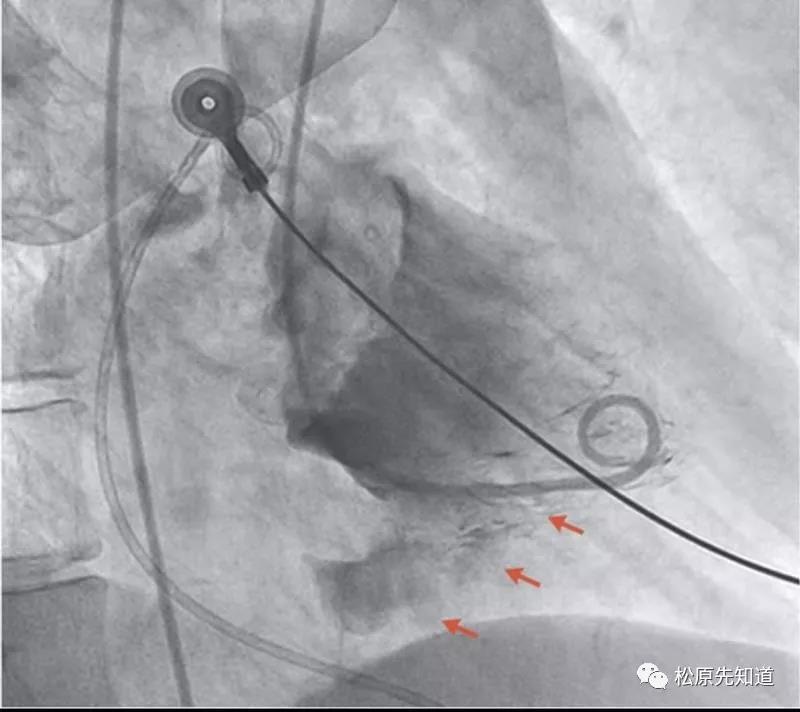

患者进入导管室后心电监护显示,宽QRS波,心率40/分,患者血压测不出,并随即出现心室颤动,患者躁动,导管室医护人员立即进入抢救状态,给以心脏按压、电除颤,患者出现交感风暴,反复室颤30余次,多次给予胺碘酮、艾司洛尔以及多巴胺、肾上腺素、阿托品等药物抢救治疗,并且穿刺右侧股静脉,置入临时起搏器。行冠脉造影检查结果提示:右冠近端100%闭塞。立即开通闭塞血管,植入一枚支架,右冠血流恢复正常。患者血流动力学不稳定,给予多巴胺等药物维持,并置入IABP,经过紧张有序的抢救,患者终于转危为安。